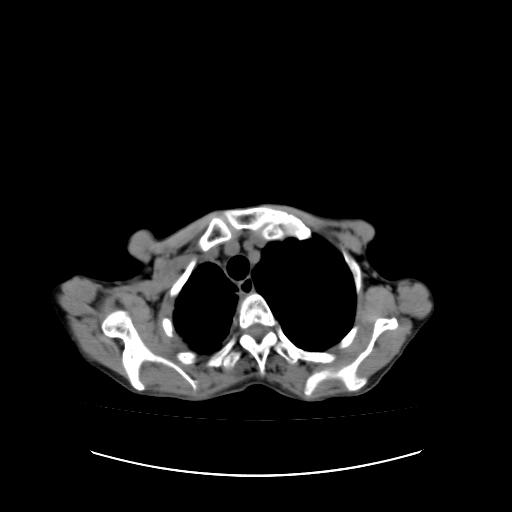

标题: CT16930:女 59 胸痛6个月 胸水脱落细胞学见瘤细胞 [打印本页]

标题: CT16930:女 59 胸痛6个月 胸水脱落细胞学见瘤细胞

右侧胸膜增厚,局部呈结节状增厚,右侧胸腔少量积液。双肺未见确切肿块影。纵隔未见淋巴结肿大。气管、支气管通畅。考虑右侧胸膜间皮瘤(恶性?)可能性大。不除外癌性胸膜炎。

右侧胸廓塌陷,右侧胸膜广泛增厚并见多发胸膜结节,右侧少量胸腔积液并包裹。

右侧广泛胸膜增厚,局部呈结节状增厚,右侧胸腔少量积液。双肺未见确切肿块影。纵隔未见淋巴结肿大。气管、支气管通畅。考虑右侧胸膜间皮瘤(恶性?)可能性大。支持!